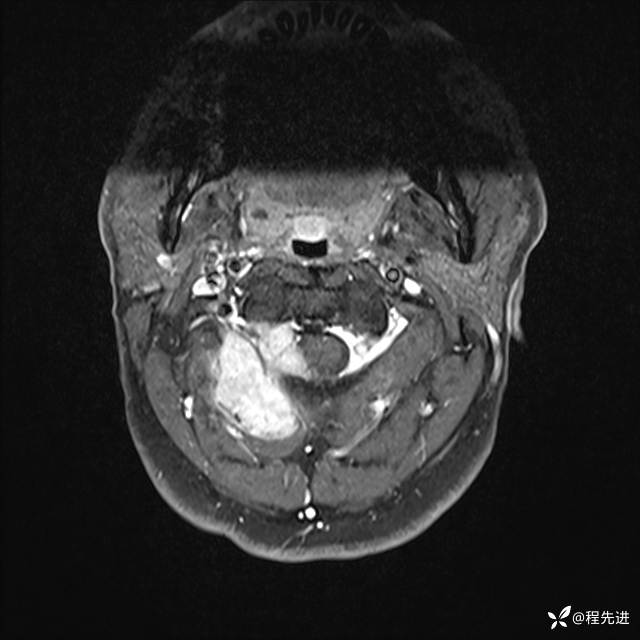

MRI平扫+增强:

T1增强: